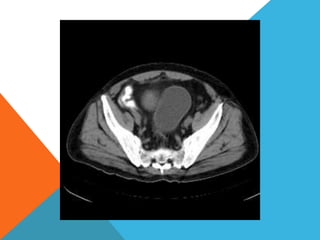

El paciente presentó síntomas de sangrado digestivo y pérdida de peso. Exámenes revelaron gastritis crónica asociada a H. pylori. Un tumor fue descubierto en una colonoscopia normal. La cirugía removió un tumor fibroide solitario, una rara neoplasia mesenquimal que usualmente crece lento y tiene bajo potencial de malignidad. El pronóstico después de la remoción quirúrgica es generalmente bueno.